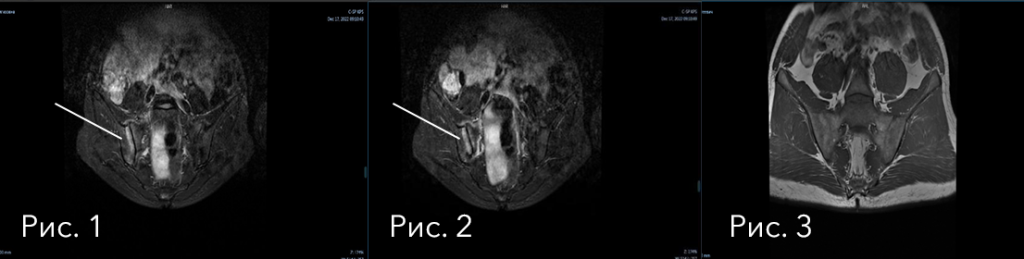

На снимках ниже (рис. 4-5), через полгода лечения генно-инженерными биологическими препаратами, мы видим абсолютную МРТ-ремиссию.

Помимо МРТ-ремиссии ревматологам удалось добиться и других точек оценки эффективности:

• в улучшении качества жизни пациентки: по результатам опросника здоровья пациента (PHQ-9) удовлетворенность качеством жизни увеличилась на 70%;

• по индексам активности анкилозирующего и псориатического спондилита (ASDAS, BASDAI) мы добились низкой активности заболевания (BASDAI = 5,2 -> 3,15; ASDAS = 3,5→2,06)

Достигнута комплексная ремиссия: клиническая, лабораторная и МРТ-ремиссия - результат лечения ГИБТ препаратами у пациентки.